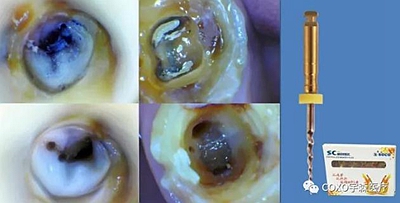

6,根管器械折斷

1.嚴(yán)格控制器械在根管內(nèi)的使用次數(shù)

2.充分了解根管系統(tǒng),在狹窄處切勿強(qiáng)行通過(guò)

3.對(duì)復(fù)雜的根管:如分叉或融合的根管、急彎的根管、S形根管,鈣化根管使用新的鎳鈦器械預(yù)備,充分潤(rùn)滑、沖洗、多提拉、使用專用銼,必要時(shí)結(jié)合手?jǐn)U銼完成根管預(yù)備

4.不能用力過(guò)猛,在感到阻力時(shí)應(yīng)用輕微的力“啄”的手法運(yùn)動(dòng),每次前進(jìn)1mm,直到到達(dá)工作長(zhǎng)度。

6.常規(guī)使用EDTA

7.次氯酸鈉液沖洗

8.每次使用擴(kuò)銼前,仔細(xì)檢查器械的表面, 一旦發(fā)現(xiàn)有缺陷立即棄用。